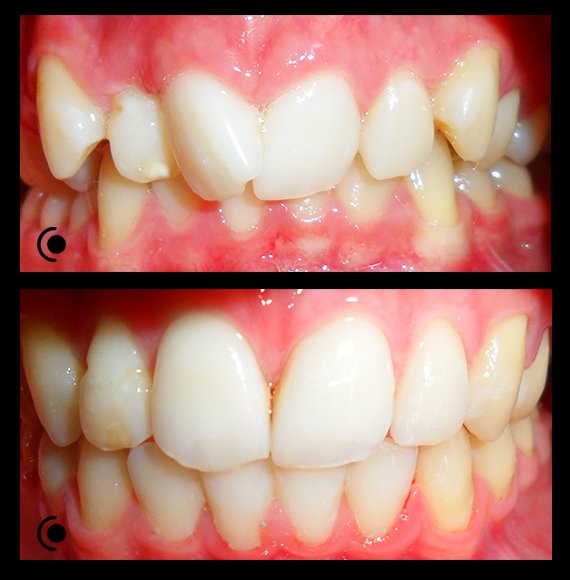

O našoj kvaliteti najbolje govore naši rezultati!

Centar za ortodonciju Petra Džapo